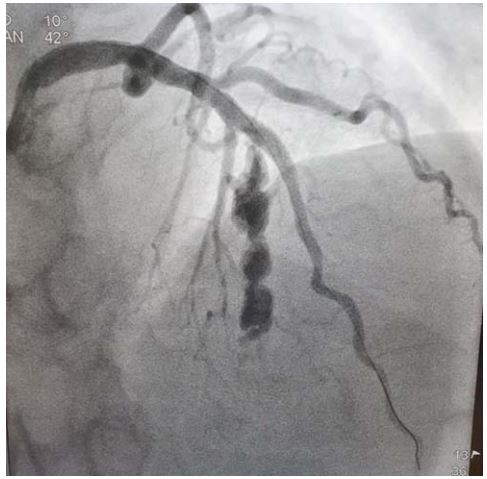

Mulher de 67 anos hipertensa e dislipidemia procurou atendimento médico com dor torácica de forte intensidade com duração há 2 horas. ECG de admissão revelou supra ST na parede anterior. Foi submetida a angioplastia primária. O controle após a angioplastia é representado a seguir:

Qual é diagnóstico mais provável: